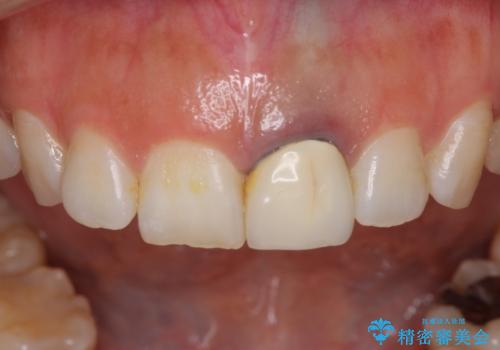

- 前歯をメタルの被せものにしており、セラミックに変えるのを希望された患者様です。

土台も金属だったため、歯がかなり黒く変色していました。

色は完全にとるのが不可能であることをご了承頂いた上で、土台と被せものの治療を行いました。

今回は歯自体が黒くなって歯茎から透けて見えている黒ずみのため、セラミック治療で改善させることは困難だというお話をしました。その上でできる範囲できれいに治療することになりました。